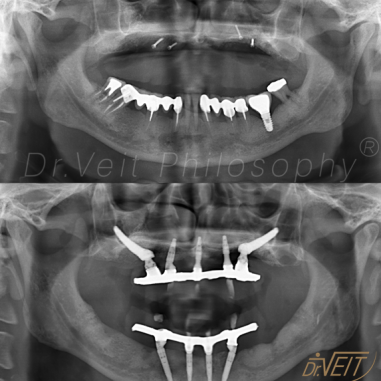

Reabilitação Oral com Implantes Zigomáticos

Arte de reabilitar os casos  “impossíveis”. Pacientes que buscam a reabilitação oral podem conquistar um belo sorriso com segurança, mais conforto e tranquilidade com o uso do Implante Zigomático. A técnica possui o diferencial de realizar a implantação no osso zigomático e é indicada para casos de perda óssea maxilar avançada.